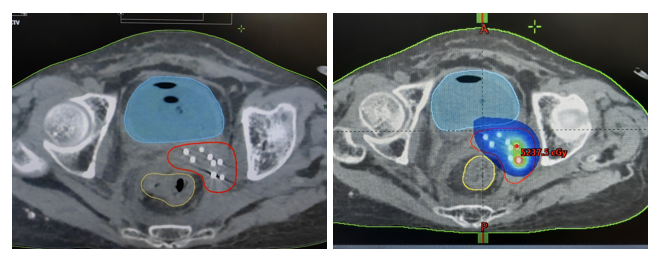

操作完成后再次采集患者盆腔CT定位图像,然后由医生在二次CT图像上进行靶区勾画,物理师赵强设计制作了放射源分布合理的治疗计划,审核通过后对该名患者实施了高剂量率三维插植后装放疗。

经对比,本病例固定模板插植治疗与3D打印模板治疗的肿瘤治疗靶区HR-CTV(高危临床靶区)D90,剂量适形度,后者明显提高。

(放射源分布合理的治疗计划)